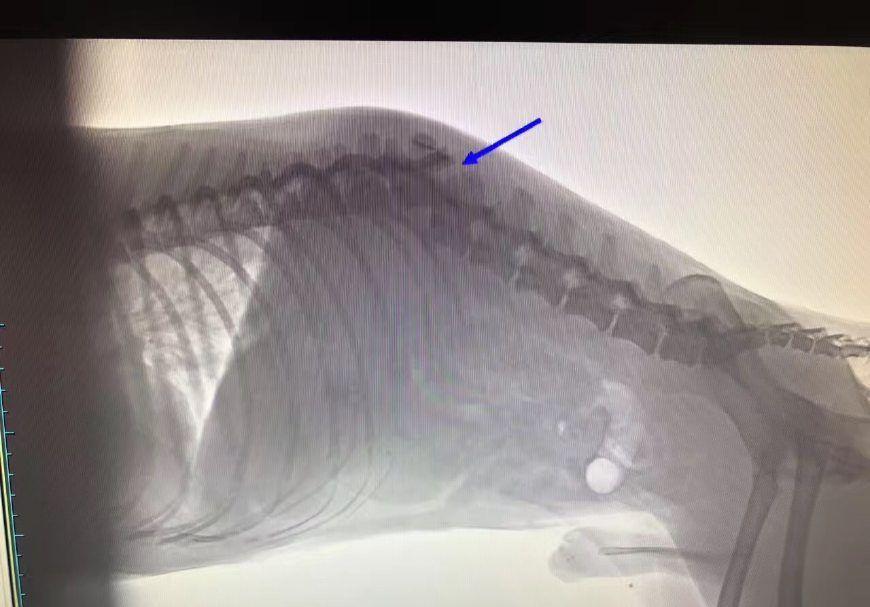

犬侧视x线闭合于胸廓标准和胸部,颈骨至背骨疼痛区

犬类脊柱x射线

狗脊椎x光片